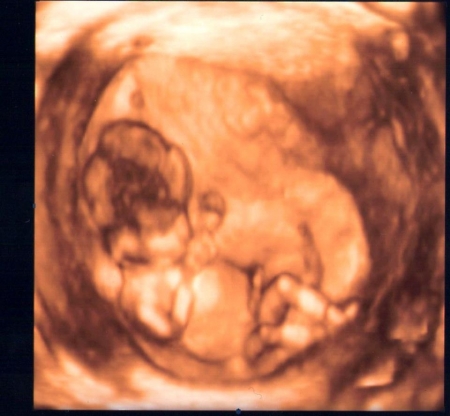

Plod o velikosti 70 mm ve 13. týdnu těhotenství (12+3)

Jak tělo roste a mění se? Vývoj zaznamenávají také končetiny plodu.

Autoři: Texty na základě zdroje www.babyonline.cz, vlastní praxe a znalostí zpracovala MUDr. Jarmila Halová, doplnil a upravil MUDr. Ondřej Šimetka, přednosta Porodnicko-gynekologické kliniky FN Ostrava, kde byly rovněž pořízeny ultrazvukové snímky, autor: MUDr. M. Pětroš. Poslední korekturu v srpnu 2024 provedla: MUDr. Veronika Ťápalová (Gynekologicko-porodnická klinika LF MU a FN Brno).